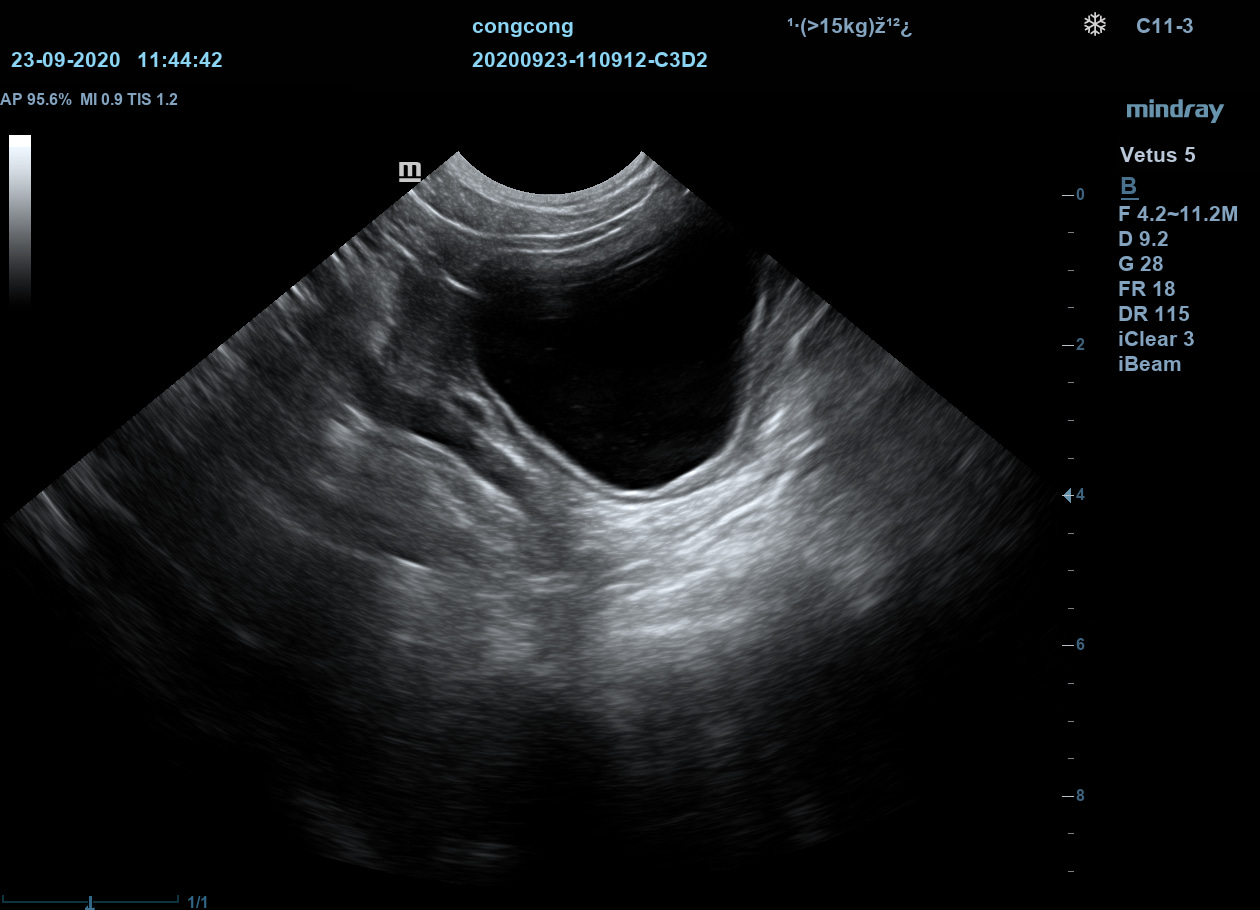

Ветеринарный ультразвуковой аппарат Mindray Vetus 5 использует новейшие технологии и ПО и позволяет проводить скрининг внутренних органов животных, получая чёткие и достоверные данные об их структуре, размерах и расположении.

Позволяет получать УЗИ-изображения с учётом анатомических особенностей животных.

Подразделяет животных по размеру и весу для максимально точной диагностики.

По сравнению с традиционными датчиками, в датчиках с технологией ComboWave используется новый тип композитного пьезоэлектрического материала. Благодаря свойствам этого материала, оптимизируется акустический спектр и подавляются акустические шумы.

iClear

Визуализация с подавлением зернистости. Улучшение качества изображения за счет автоматического распознавания структуры тканей.